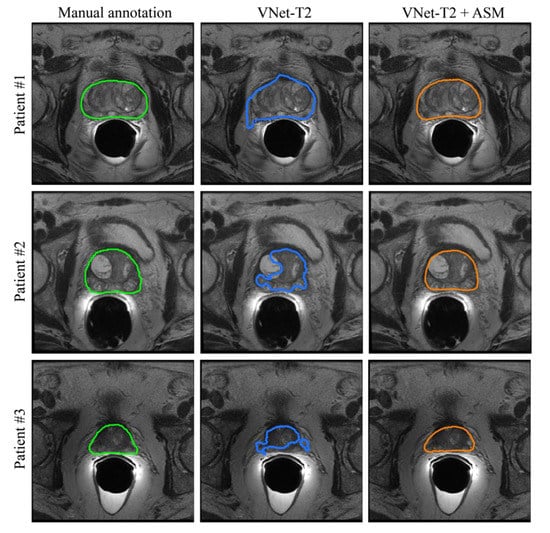

3. Results

3.1. Ablation Study